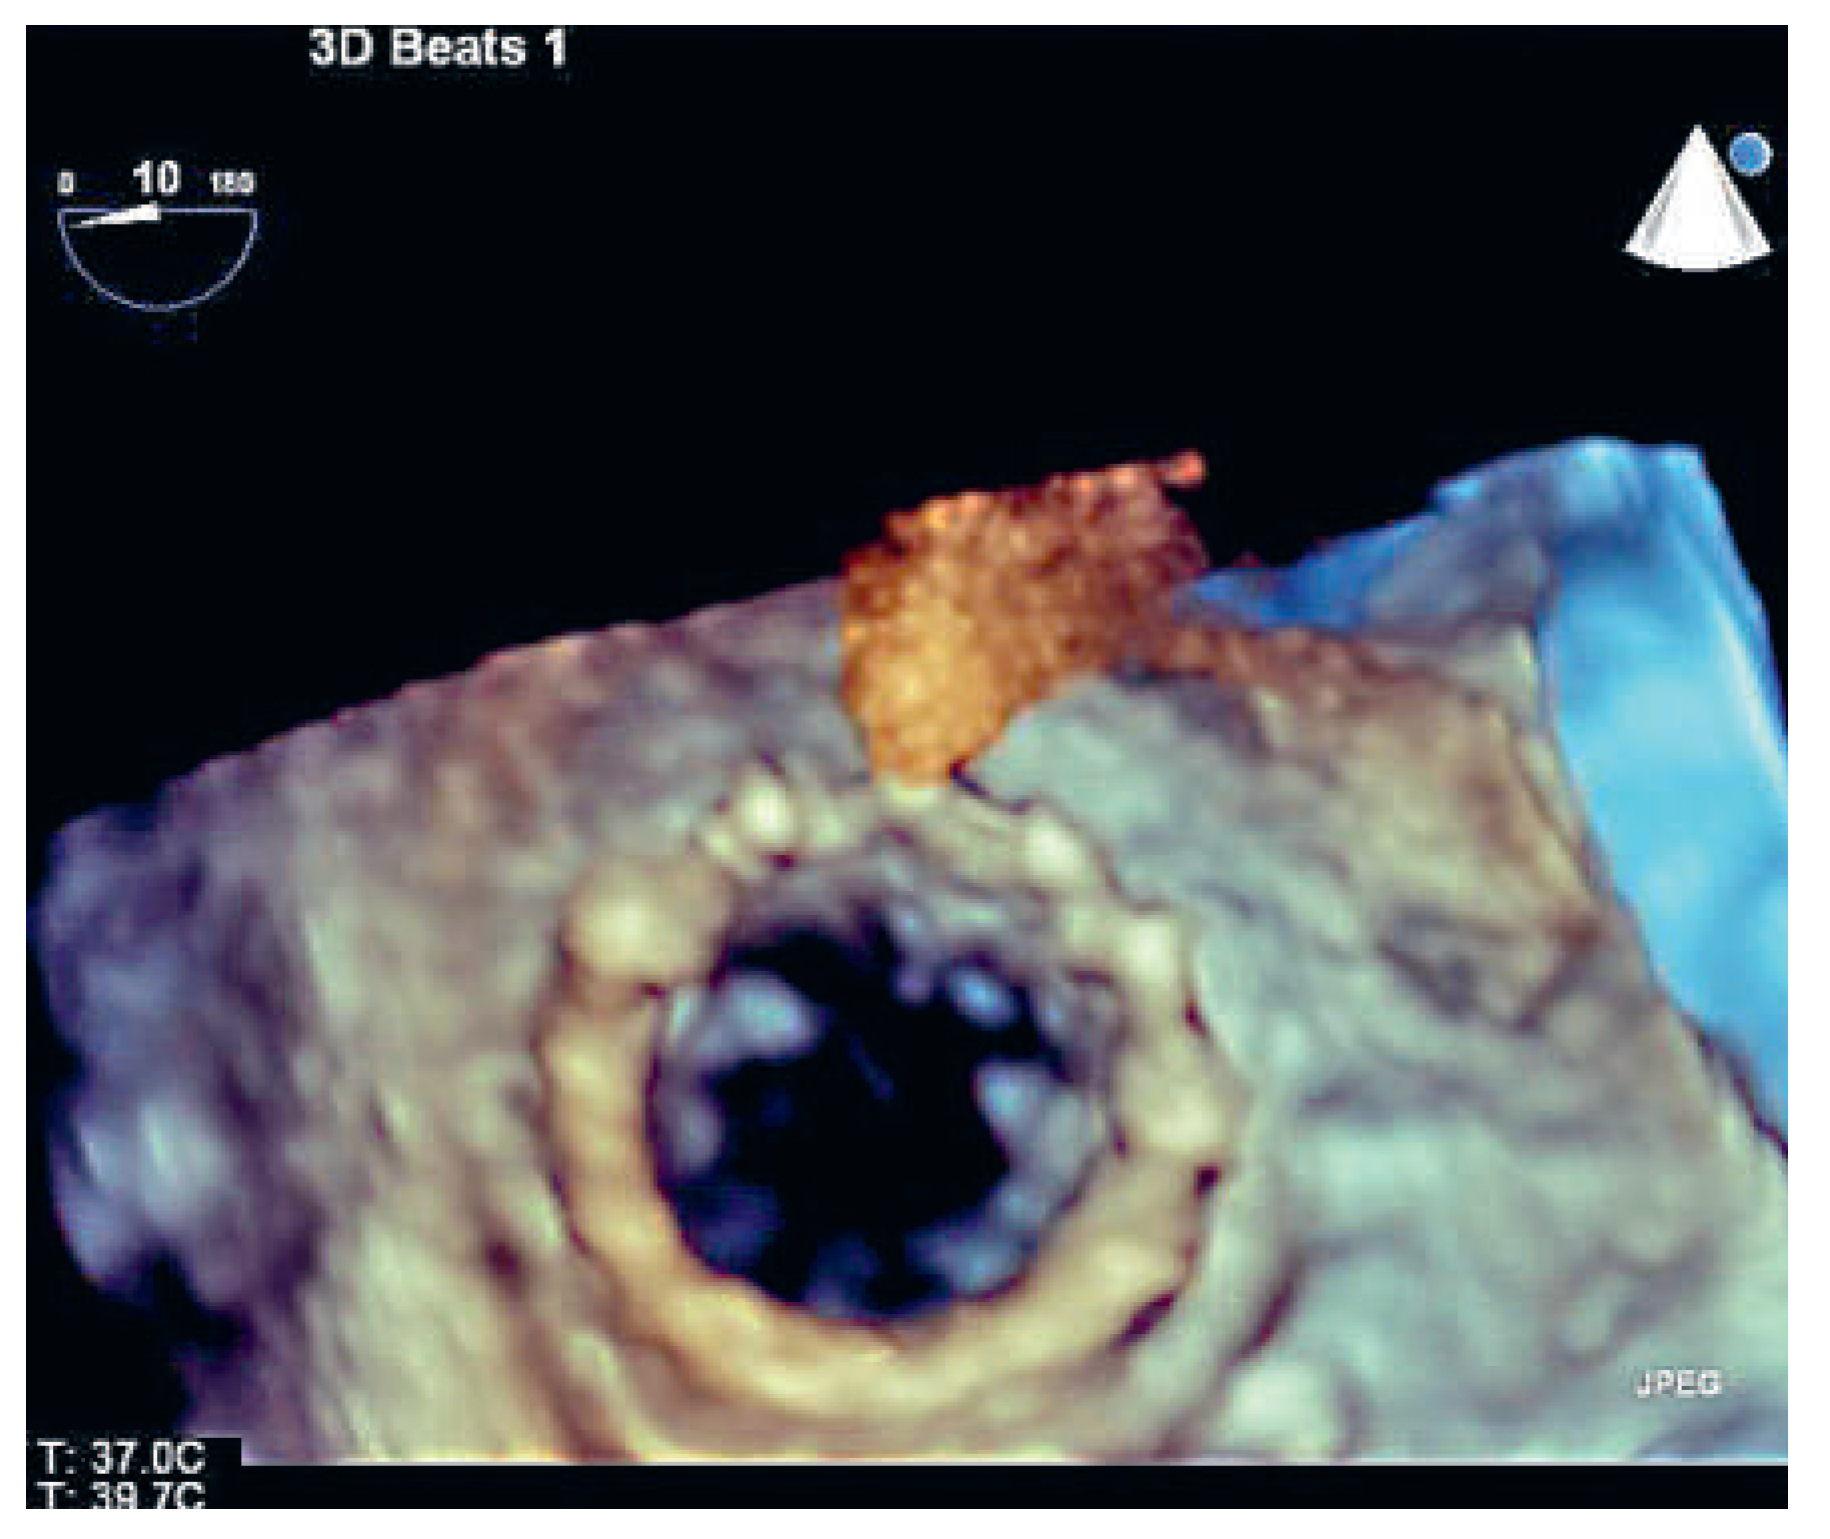

A Valve-in-Valve Approach for Ebstein’s Anomaly

Case report